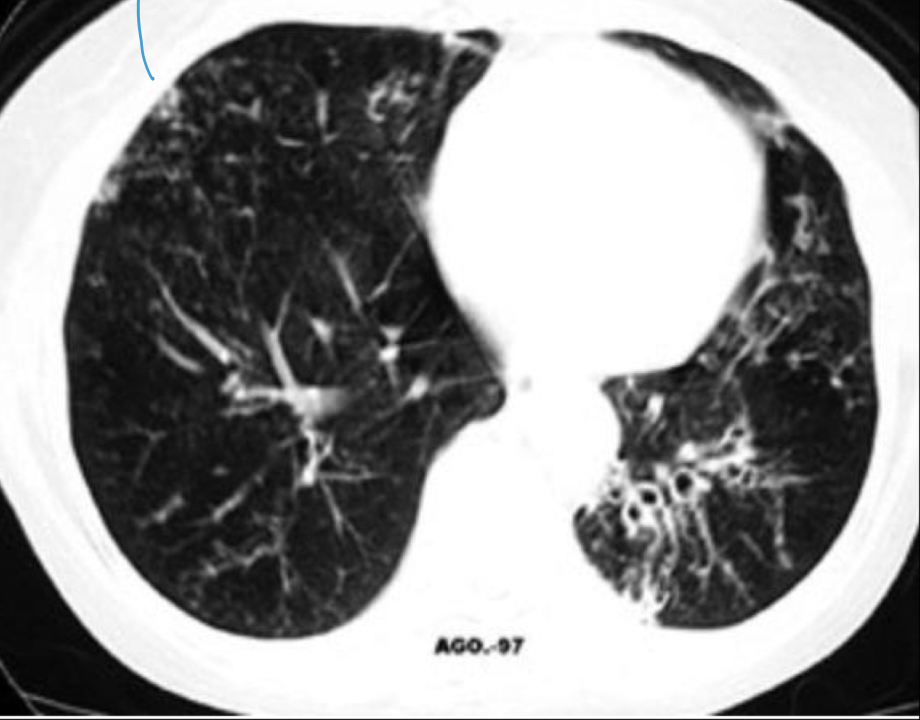

¿Qué buscamos en una TC para asma?

A

• Para enfermedades asociadas (aspergilosis, neumonía)

• Hiperclaridad

• Engrosamiento bronquial

• Atrapamiento de aire

¿De qué enfermedad nos habla?